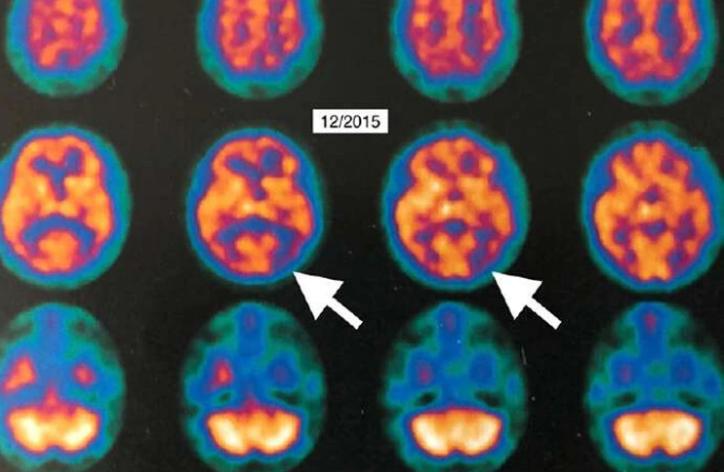

Al comparar las imágenes de la PET realizada un mes después de finalizado el tratamiento OHB con los estudios anteriores, se hallaron cambios visibles del metabolismo cerebral entre el 6,5% y el 38 por ciento.

El trabajo incluyó imágenes en 3D de la PET que reconstruyen la superficie del cerebro de la mujer, donde se pueden ver los cambios. “La PET se utiliza en el mundo como un biomarcador en oncología y cardiología para evaluar las respuestas a los tratamientos”, dijo Fogarty en la página de LSU. “Ahora tenemos un sistema de biomarcación irrefutable que muestra que esta intervención tiene potencial allí donde antes no existía una esperanza real de recuperación de la demencia”.